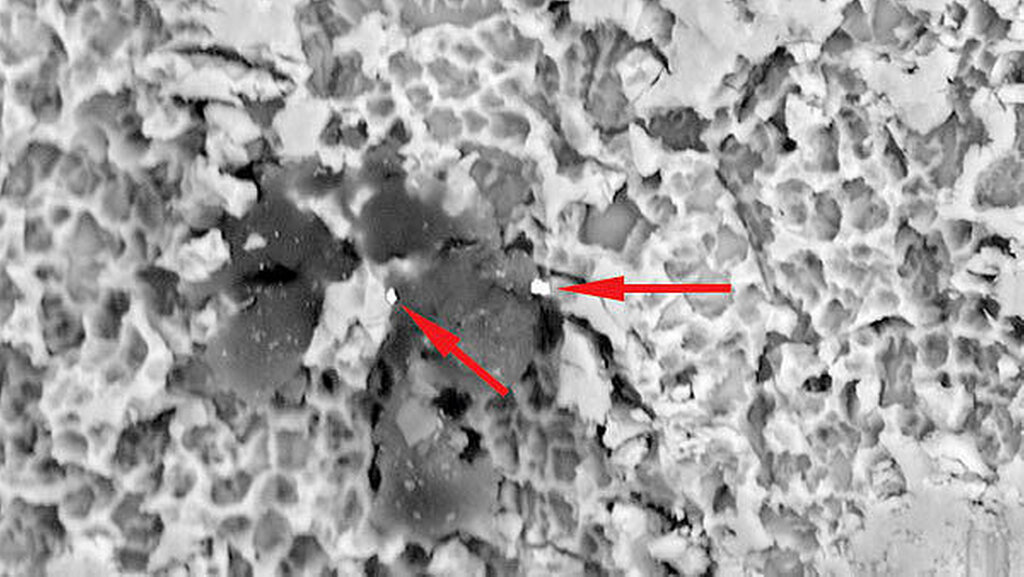

Die Implantatmuster werden anschließend nach dem in der Akkreditierung festgelegten Analyseverfahren systematisch gescannt, die gegebenenfalls gefundenen Rückstände und Partikel vermessen sowie mittels energiedispersiver Röntgenspektroskopie (EDX) einer qualitativen und quantitativen Elementanalyse zugeführt. Die durch rückgestreute Elektronen erzeugten Materialkontrastbilder eignen sich dabei besonders für diese Analysen, da sich Fremdpartikel durch andere Grauwerte im Bild deutlich abheben und so gezielte EDX-Spotanalysen erlauben.